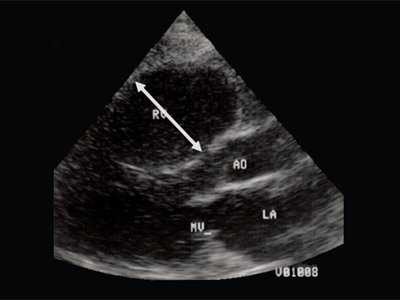

Рис. 2. Длинная ось сердца. Объемная перегрузка правого желудочка при дефекте межпредсердной перегородки. Объем сброса крови превышает 200% МОС. Отмечается выраженная дилатация правого желудочка.

Рис. 3. Объемная перегрузка правого желудочка при дефекте межпредсердной перегородки. В- и М-сканирование. Стрелкой показан парадоксальный характер движения межжелудочковой перегородки.

Для левого желудочка признаком объемной перегрузки являются увеличение полости левого предсердия и желудочка, а также экскурсии межжелудочковой перегородки и миокарда задней стенки левого желудочка (рис. 4).

Рис. 4. Объемная перегрузка левых отделов сердца. В- и М-сканирование. Отмечается усиление экскурсии межжелудочковой перегородки и миокарда задней стенки левого желудочка.

IVS - межжелудочковая перегородка, MLV - миокард левого желудочка, LV и RV - левый и правый желудочек.